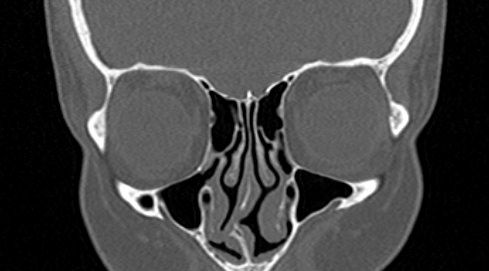

Орбиты (или глазницы) – это костные углубления в лицевом черепе, где расположены глазные яблоки, окруженные жировой клетчаткой, а также слезные железы, слезные каналы, сосуды, нервы, мышцы и связки глаза. Такая небольшая по объему область содержит важные анатомические структуры, обеспечивающие нормальную функцию органа зрения.

Кроме того, область орбиты тесно связана с близлежащими структурами – полостью черепа с расположенным в ней головным мозгом, а также с полостью носа, околоносовыми пазухами и носоглоткой. Различные патологические процессы могут развиваться как в самой глазнице, так и в околоорбитальных структурах, но при этом распространяться на область орбит.

Сложное строение глазницы и взаимосвязь с соседними анатомическими структурами затрудняет диагностику заболеваний глазного яблока и его придатков. Одним из наиболее информативных методов обследования органа зрения и окружающих тканей является мультиспиральная компьютерная томография. Кроме высокой информативности методика отличается быстротой и неинвазивностью (то есть не требует вмешательства в организм человека). Принцип получения изображений построен на применении ионизирующего излучения и разной способности тканей поглощать рентгеновские лучи.

Мультиспиральная компьютерная томография лучше всего визуализирует ткани с высокой плотностью, к которым, в частности, относится костная ткань. Это делает КТ незаменимой при диагностике травматических повреждений глазниц, а также для выявления инородных тел орбит.

По результатам КТ орбиты глаза врач может оценить состояние:

- костных стенок глазницы, верхней и нижней глазничных щелей;

- глазных яблок

- стекловидного тела;

- мышц глаза: нижней, верхней, косой, прямых мышц (латеральной и медиальной);

- глазничной артерии и вены;

- зрительных нервов;

- слезных желез;

- ретробульбарной (расположенной позади глазного яблока) клетчатки.